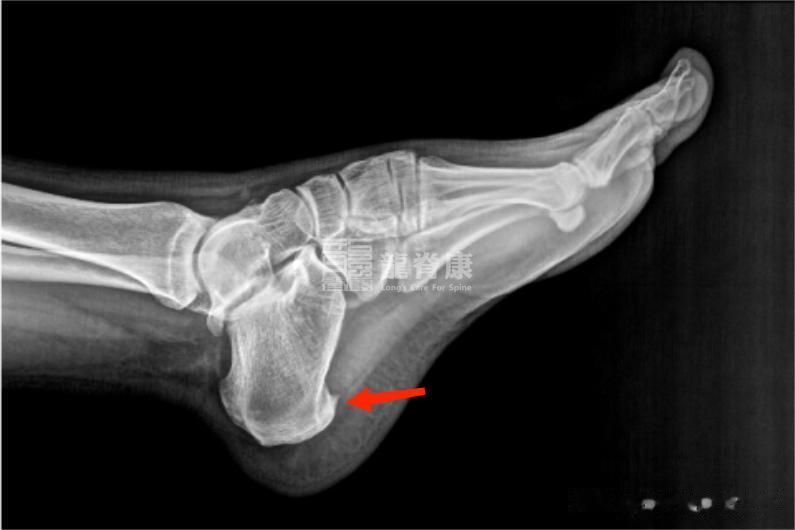

4、足跟骨刺

足跟骨刺是跟骨下缘的异常骨质增生,本身可能不直接引起疼痛,但刺激周围软组织时会引发疼痛和炎症。

主要表现为足跟痛和行走困难,可能伴足底广泛压痛。行走或站立时加重,休息后缓解。主因长期过度负重和不适当锻炼,年龄增长导致的跟骨退行性改变也是常见原因。